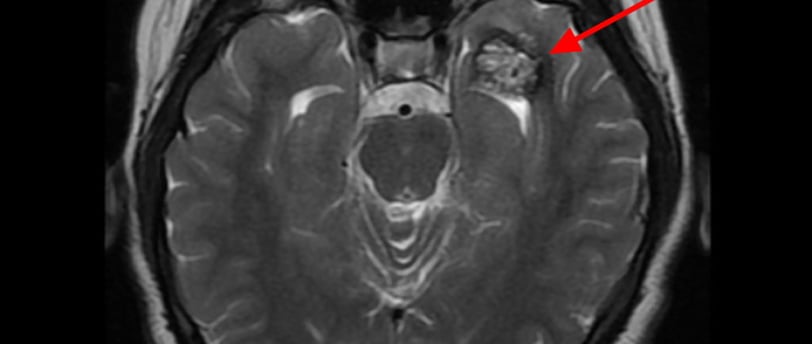

O diagnóstico de cavernoma é frequentemente feito por meio de ressonância magnética (RM) cerebral, que oferece alta sensibilidade para detectar essas lesões. As principais características radiológicas incluem:

Aspecto “popcorn”: Presença de áreas heterogêneas que representam hemorragias recentes e antigas, tecido fibroso e calcificação.

Halo Hipointenso em T2: Este sinal é causado pela deposição de hemossiderina ao redor da lesão, indicando hemorragias prévias.

Realce Mínimo ou Inexistente: Diferencia os cavernomas de outras malformações vasculares, como angiomas venosos ou arteriovenosos.